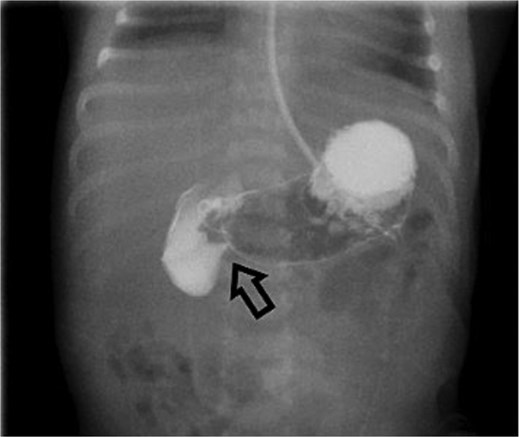

On Day 3 of life, she developed multiple episodes of bilious emesis and passed meconium-stained stools. An abdominal radiograph revealed gas-filled, non-distended bowel loops on the right and absence of small bowel gas on the left (Fig. 1), raising suspicion for malrotation. An upper GI (UGI) series confirmed abnormal duodenal positioning and obstruction, suggestive of malrotation with volvulus (Fig. 2). Emergent Ladd’s procedure was performed, revealing midgut volvulus with cloudy peritoneal fluid but viable bowel.

Abdominal X-ray shows nonspecific gas pattern with gas-filled, nondistended bowel loops on the right. Absence of small bowel gas on the left raises suspicion for malrotation.